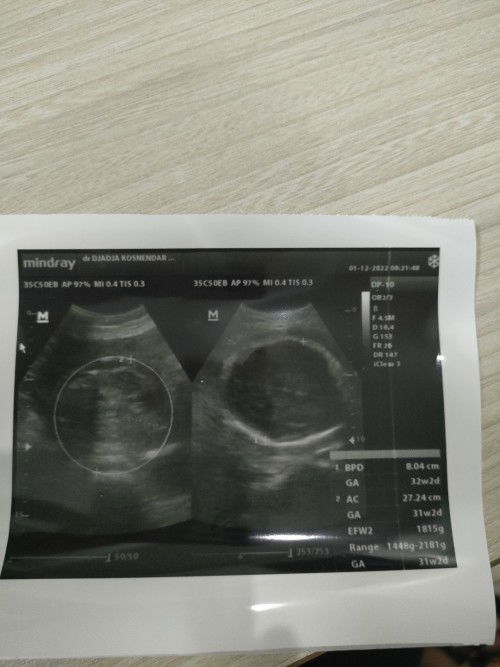

Usg kehamilan

Bun mau tanya .ini berat janin nya brapa ya.normal ga d usia 32 minggu.soalnya td sya usg d rmh skit.tp dktrnya ga bnyak ngbrol Sya jg lpa ga nanya soalna buru2. Mff ya bunn brg kali bunda tau .soalnya sya bru prtma hamil